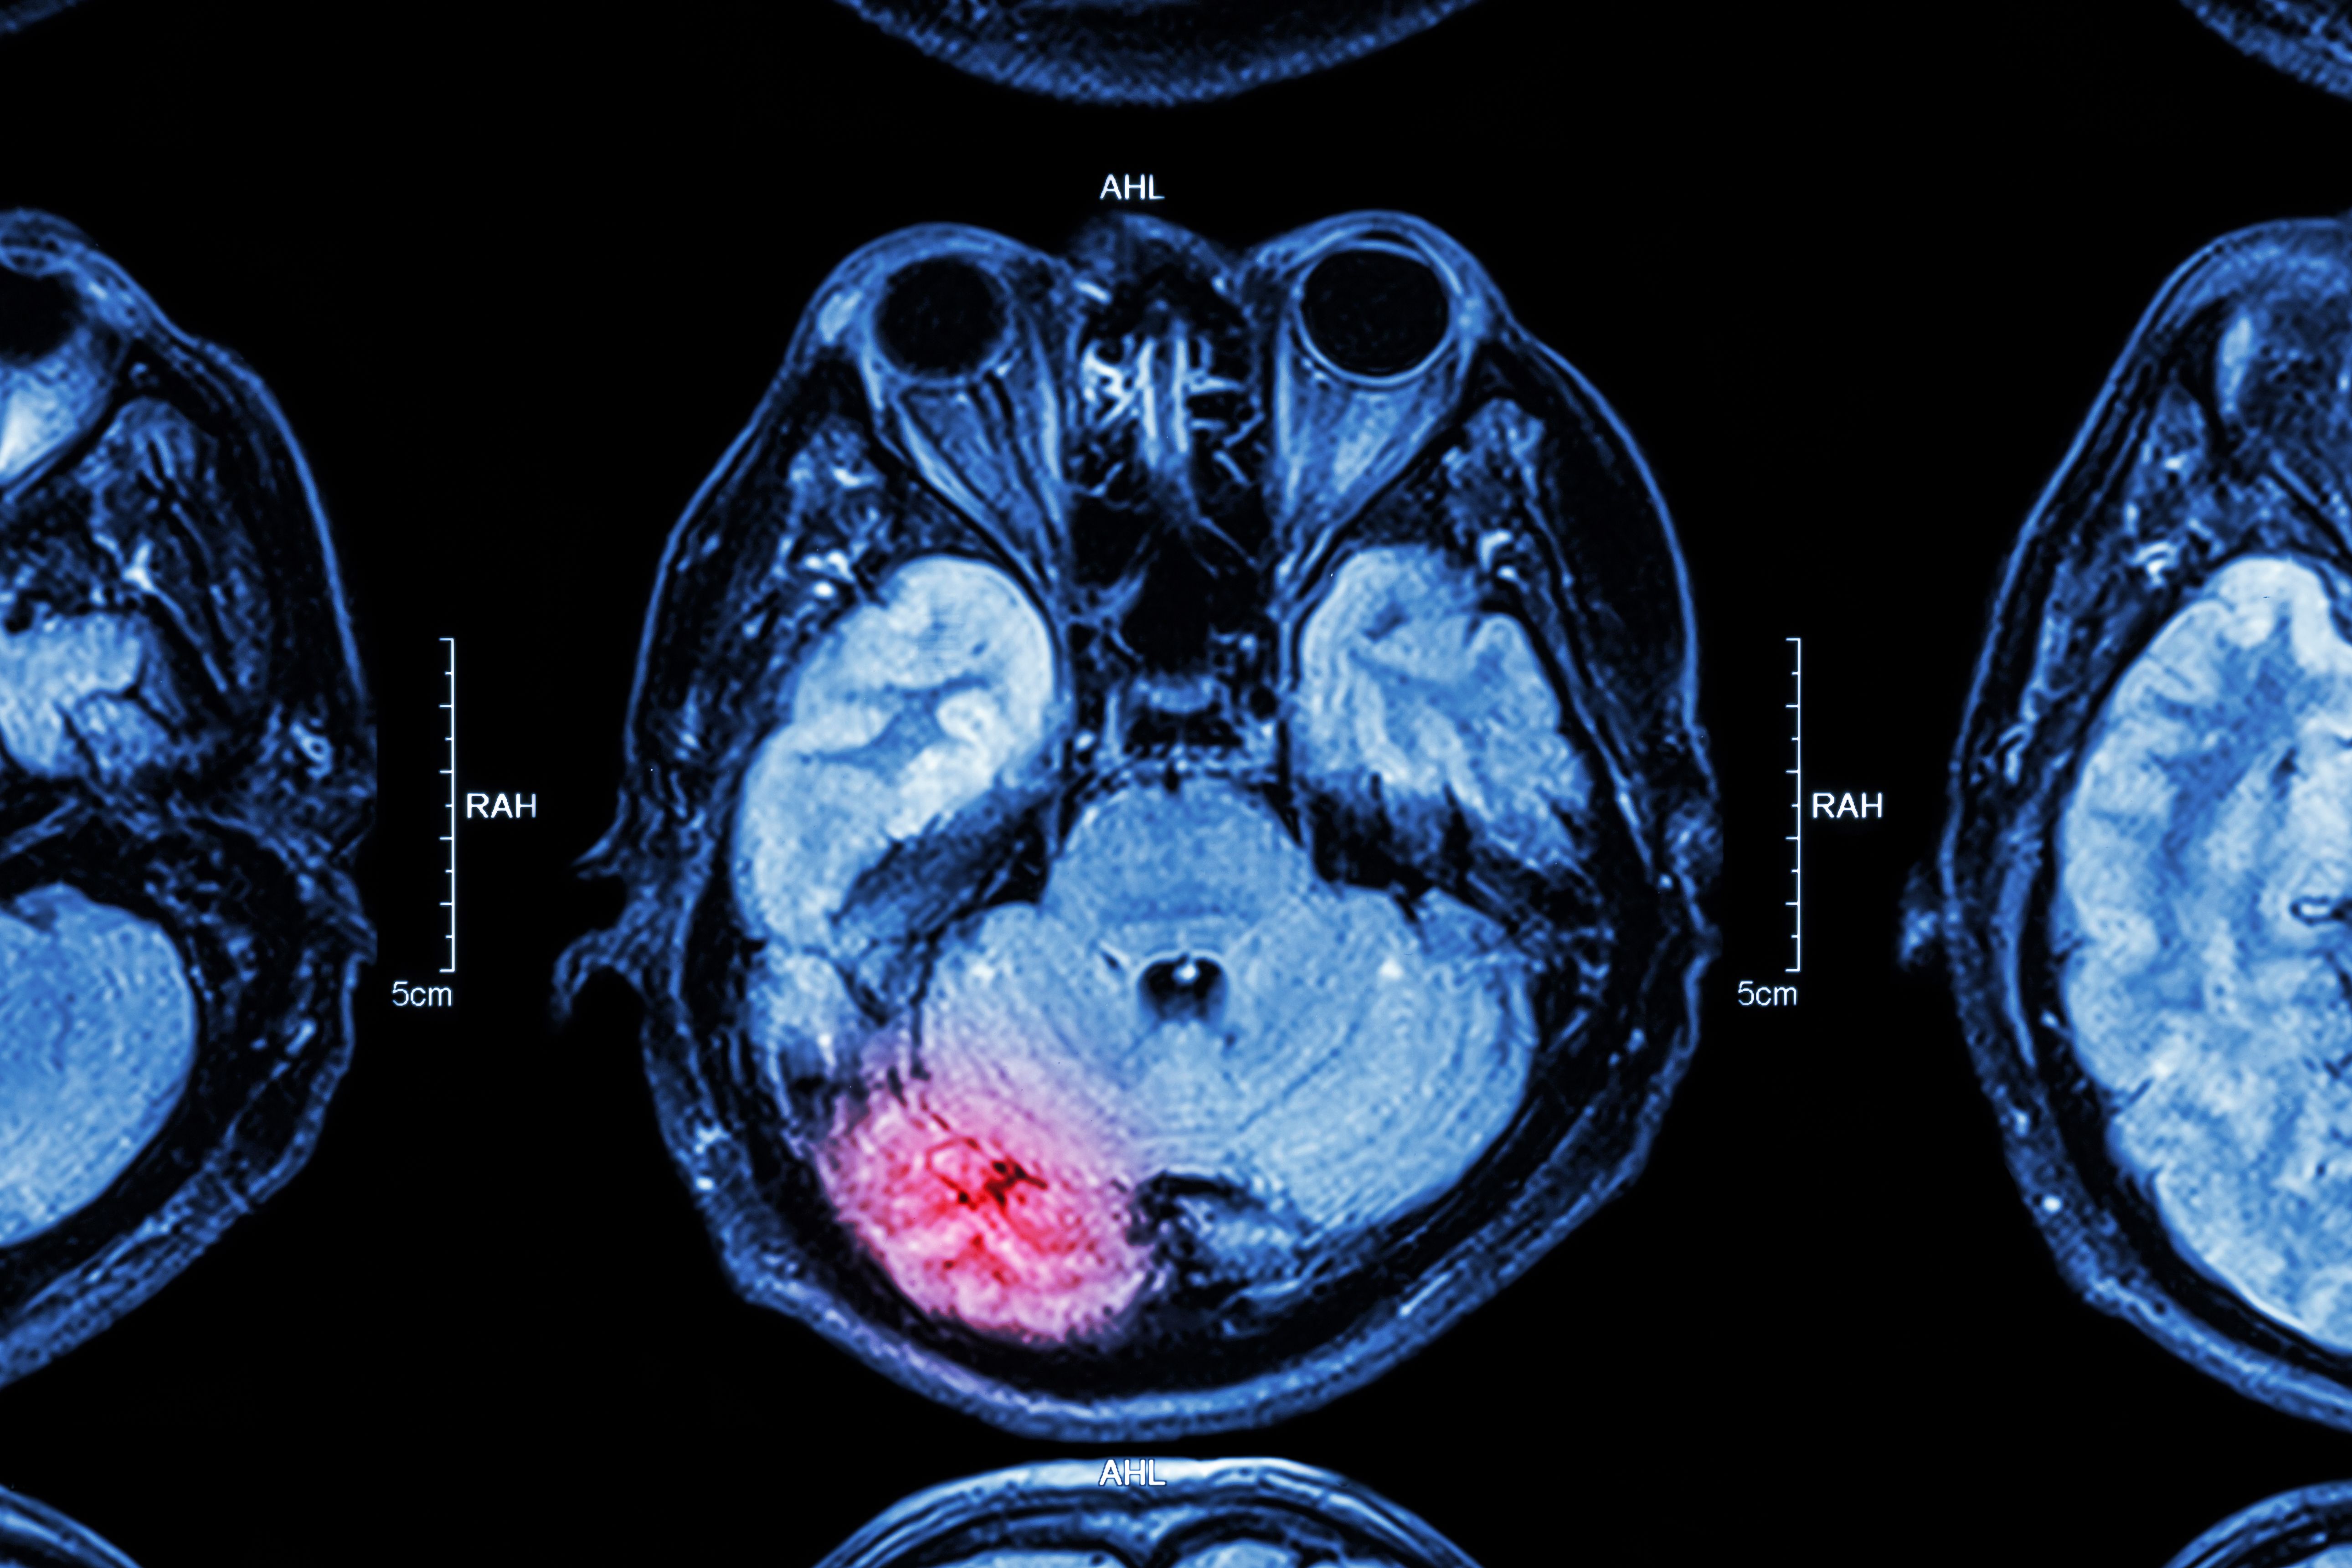

- Stroke: A sudden interruption in blood flow to the brain.

- Aneurysms: A bulging blood vessel that can burst and cause bleeding in the brain.